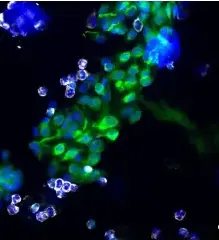

Example images from patient blood samples

Single mesenchymal CTCs - breast

Examples of Portrait+ CTC staining kit samples